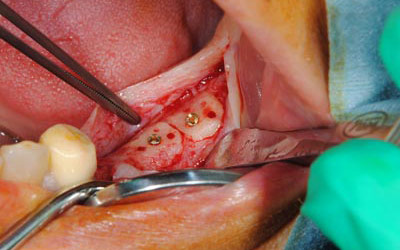

• インプラントを埋入するためには、骨を増やさなければならず、患者様ご自身の骨を移植する、自家骨移植術を行なうこととしました。写真、青色の矢印で示す、智歯周辺の骨を採取し、黄色の矢印の部位に骨片を移植、チタン製の小さなスクリューで骨片を固定するという手術を行いました。細く、白く映っているのが骨を固定したミニスクリューです。

• 写真は、実際の手術の写真で、丸く採取された骨片が、スクリューで固定されています。